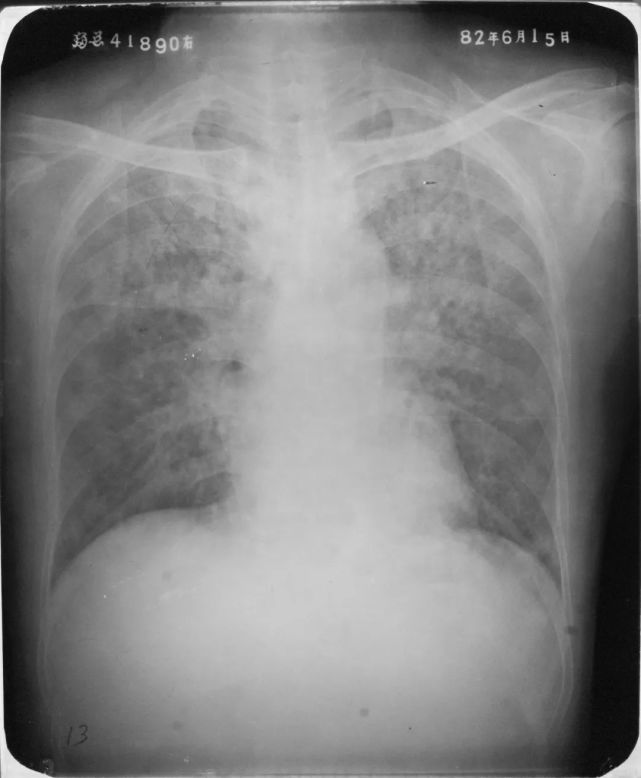

两肺支气管肺炎

图片

胸部正位片示:两肺多发不规则的小片状或斑片状边缘模糊的致密阴影,阴影密度不均,中间密度高,边缘淡,局部融合呈片状分布